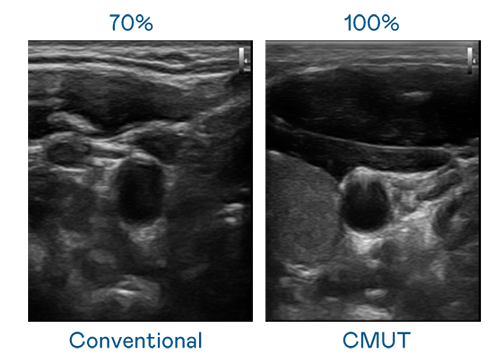

CMUT 技术是一种用电容式微机电元件来产生超音波讯号的技术。与传统 PZT 压电式技术相比,CMUT 频宽增加 30%,更宽频的超音波讯号让影像解析度大幅提升,是实现高影像品质医疗超音波扫描、促进精准医疗发展的关键技术。

超音波影像的解析度高低,首先取决于探头能发出的讯号频宽。彩神Vll官网 CMUT 可提供高清晰的超音波讯号,提供高频宽、高灵敏度、影像纹理细节更高的超音波影像,协助医护人员缩短影像判读时间及利用精准的医疗影像进行诊断。